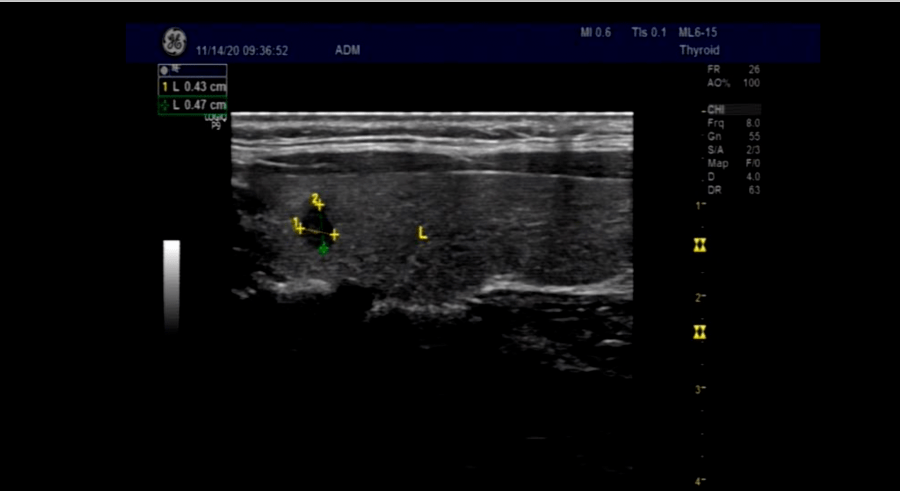

B超

左叶甲状腺见4.3x4.7mm低回声结节(纵径>横径)